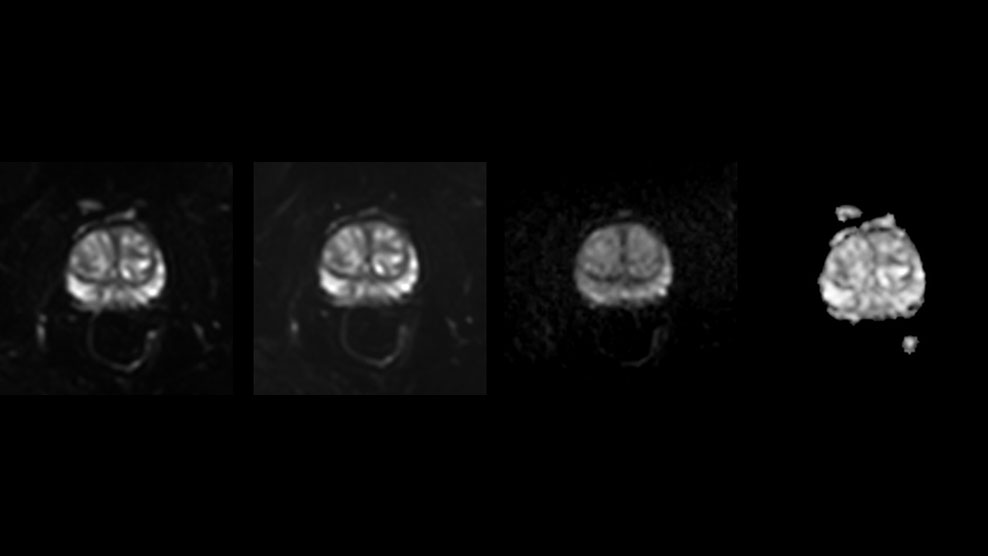

MultiVane XD helps eliminate motion for first-time-right scanning

DMG recognizes MultiVane XD motion compensation is another Philips technique that contributes to image quality and scan efficiency. “We run MultiVane XD for motion-free imaging on almost all our T2-weighted brain scans, just to reduce any repeats we might get. We know our non-contrast brain scans are going to take 20 minutes almost every time,” Mr. Duffy says.

“Using MultiVane XD still allows us to turn on dS SENSE, which significantly cuts scan time compared to what we were doing before,” he adds. “We went from a 2.5 or 3-minute scan to a 1.5-minute scan with no loss in image quality. So, it not only reduces the motion, but also reduces scan time. That gives us a little bit of extra time to speak to our patients and explain the exam a little more.”